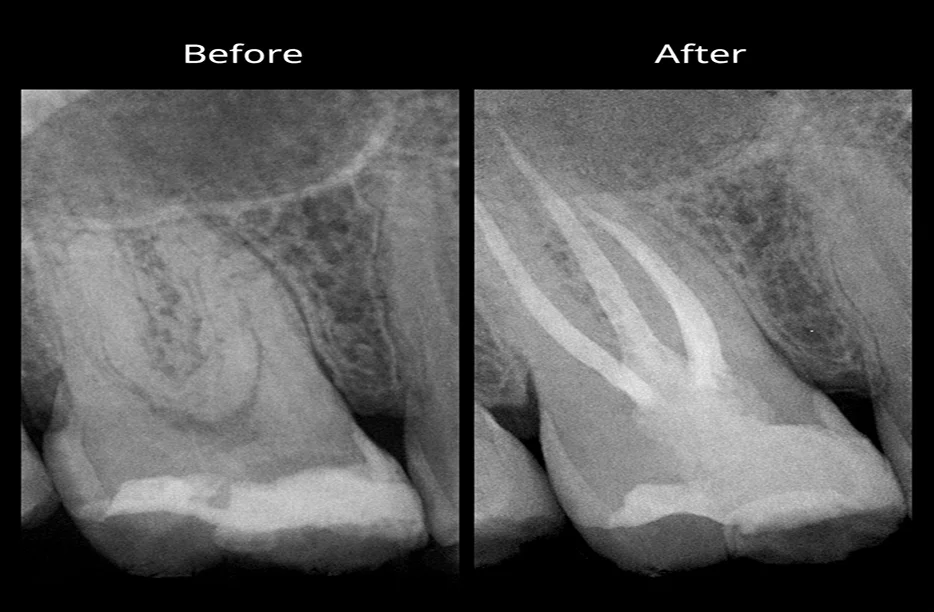

The Silent Infection

Sometimes a tooth dies without making a sound. You might not feel a thing until a routine X ray shows a dark circle at the root tip. This signifies bone loss where the infection has spread. Even without pain, a dead tooth is a ticking time bomb. It can lead to facial swelling or systemic issues if you ignore it.